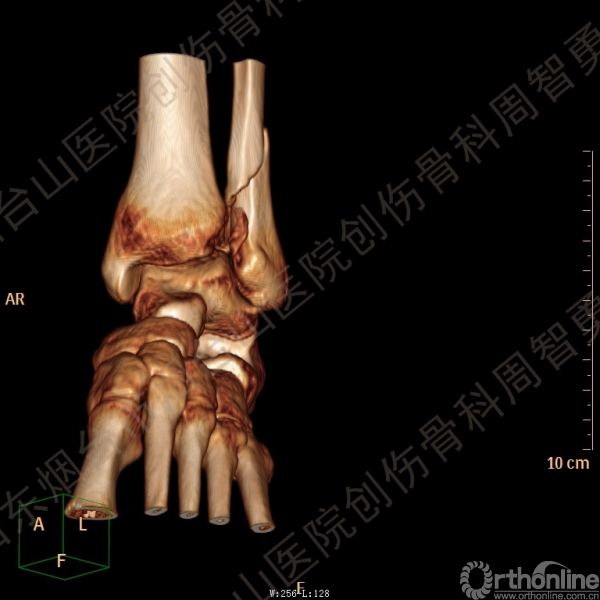

患者一般情况可,左踝关节肿胀,见皮下瘀斑,内、外、后侧有压痛,左踝关节主动运动受限,左足皮肤感觉、血供未见明显异常,左足趾各关节可主动运动。左踝关节正位X线片和CT重建示内踝内上方双层骨皮质影(图1a,c),CT示后侧骨折块分为后内侧骨折块和后外侧骨折块(图2a,b),后内侧骨折块累及内踝后丘,后丘骨折线呈冠状位(图2c),后内侧骨折块腹侧有向近端塌陷的小块骨软骨骨折块(图2d),CT也显示Chaput骨折块(图1c,2e)。

经典的后踝骨折发生于低能量旋转外力所致的踝关节骨折;标准pilon骨折见于高能量轴向暴力;而后侧pilon骨折是旋转外力和轴向暴力共同作用的结果,属于中等能量的损伤。踝关节骨折中的后踝骨折源自下胫腓后韧带的牵拉,骨折块位于后外侧,常为单一的三角形骨折块,大小从关节外片状骨折到累及胫骨远端关节面矢状径的40%(图4a)。后侧pilon骨折中的后侧骨折块较大,累及内踝后丘(三角韧带深层起点)在内的整个胫骨远端后侧,分为后内侧骨折块和后外侧骨折块,后内侧骨折块腹侧有向近端塌陷的骨软骨骨折块(图4b)。后侧pilon骨折中的内踝骨折线并不是水平位而是冠状位,可合并内踝前丘骨折。后侧pilon骨折踝关节正位X线片示特异性的内踝内上方双层骨皮质影(图1a,c)。这是由于后内侧骨折块的骨折线延伸到胫骨远端骨骺和干骺端的内侧骨皮质,其移位后的边缘成像所致。水平位CT显示后侧骨折块分为后内侧骨折块和后外侧骨折块,矢状位CT示后内侧骨折块腹侧有向近端塌陷的骨软骨骨折块。

↑ 图 2a

↑ 图 2b

↑ 图 2c

↑ 图 2d

↑ 图 2e

图 2 术前CT,显示后侧骨折块分为后内侧骨折块和后外侧骨折块(a,b),后内侧骨折块累及内踝后丘,后丘骨折线呈冠状位(c),箭头所示后内侧骨折块腹侧有向近端塌陷的小块骨软骨骨折块(d),Chaput骨折块(e)